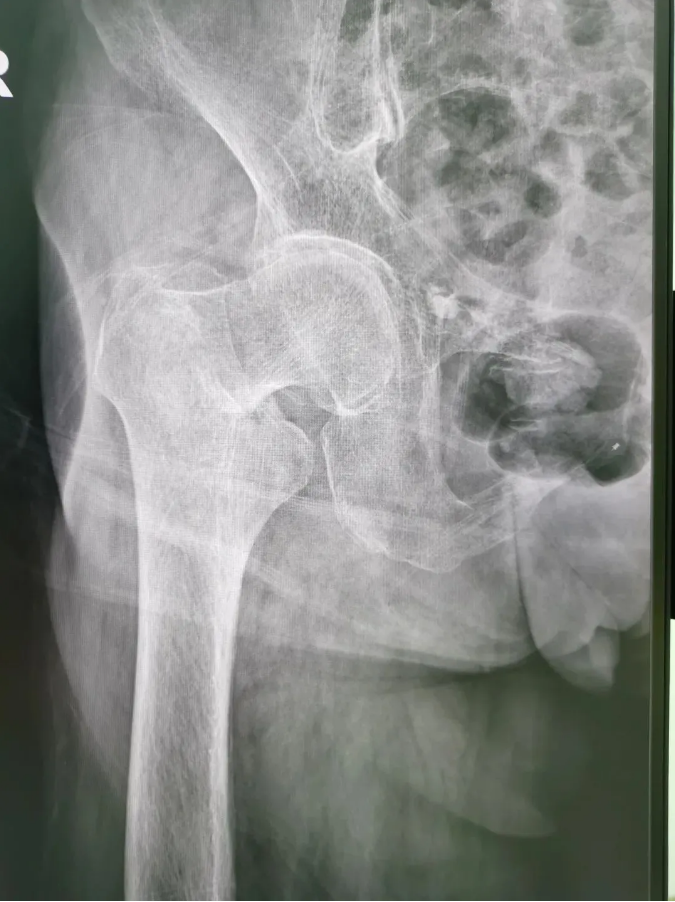

今年91歲的陳婆婆,9月份時(shí)在家不慎摔倒,右臀部著地,當(dāng)下感到髖部劇烈疼痛并活動(dòng)受限。為求進(jìn)一步治療,到順德和平外科醫(yī)院骨三區(qū)就診,該區(qū)主任楊升平主任為其診療,被診斷為“右股骨頸骨折”,需進(jìn)行右股骨頸骨折經(jīng)皮閉合復(fù)位空心螺釘內(nèi)固定手術(shù)。

術(shù)前X光

陳婆婆91歲的高齡,有高血壓和冠心病病史,通過傳統(tǒng)開刀手術(shù)治療風(fēng)險(xiǎn)較大。經(jīng)骨三區(qū)專業(yè)醫(yī)療團(tuán)隊(duì)討論,決定讓天璣?骨科機(jī)器人上場(chǎng),輔助完成微創(chuàng)手術(shù)。